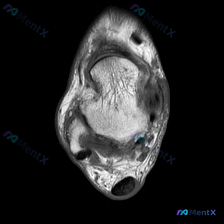

今天看到这个挺有讨论价值的读片问题,整理了完整信息和分析思路分享给大家。 病例/影像基本信息 这是一张膝关节轴位T1加权MRI图像,临床提出的问题是评估是否存在软骨异常。 我们先看这份影像的客观观察结果: 1. 整体解剖结构:髌骨、股骨远端滑车轮廓清晰,皮质骨光滑,无骨质破坏或骨皮质中断,骨髓信号大...